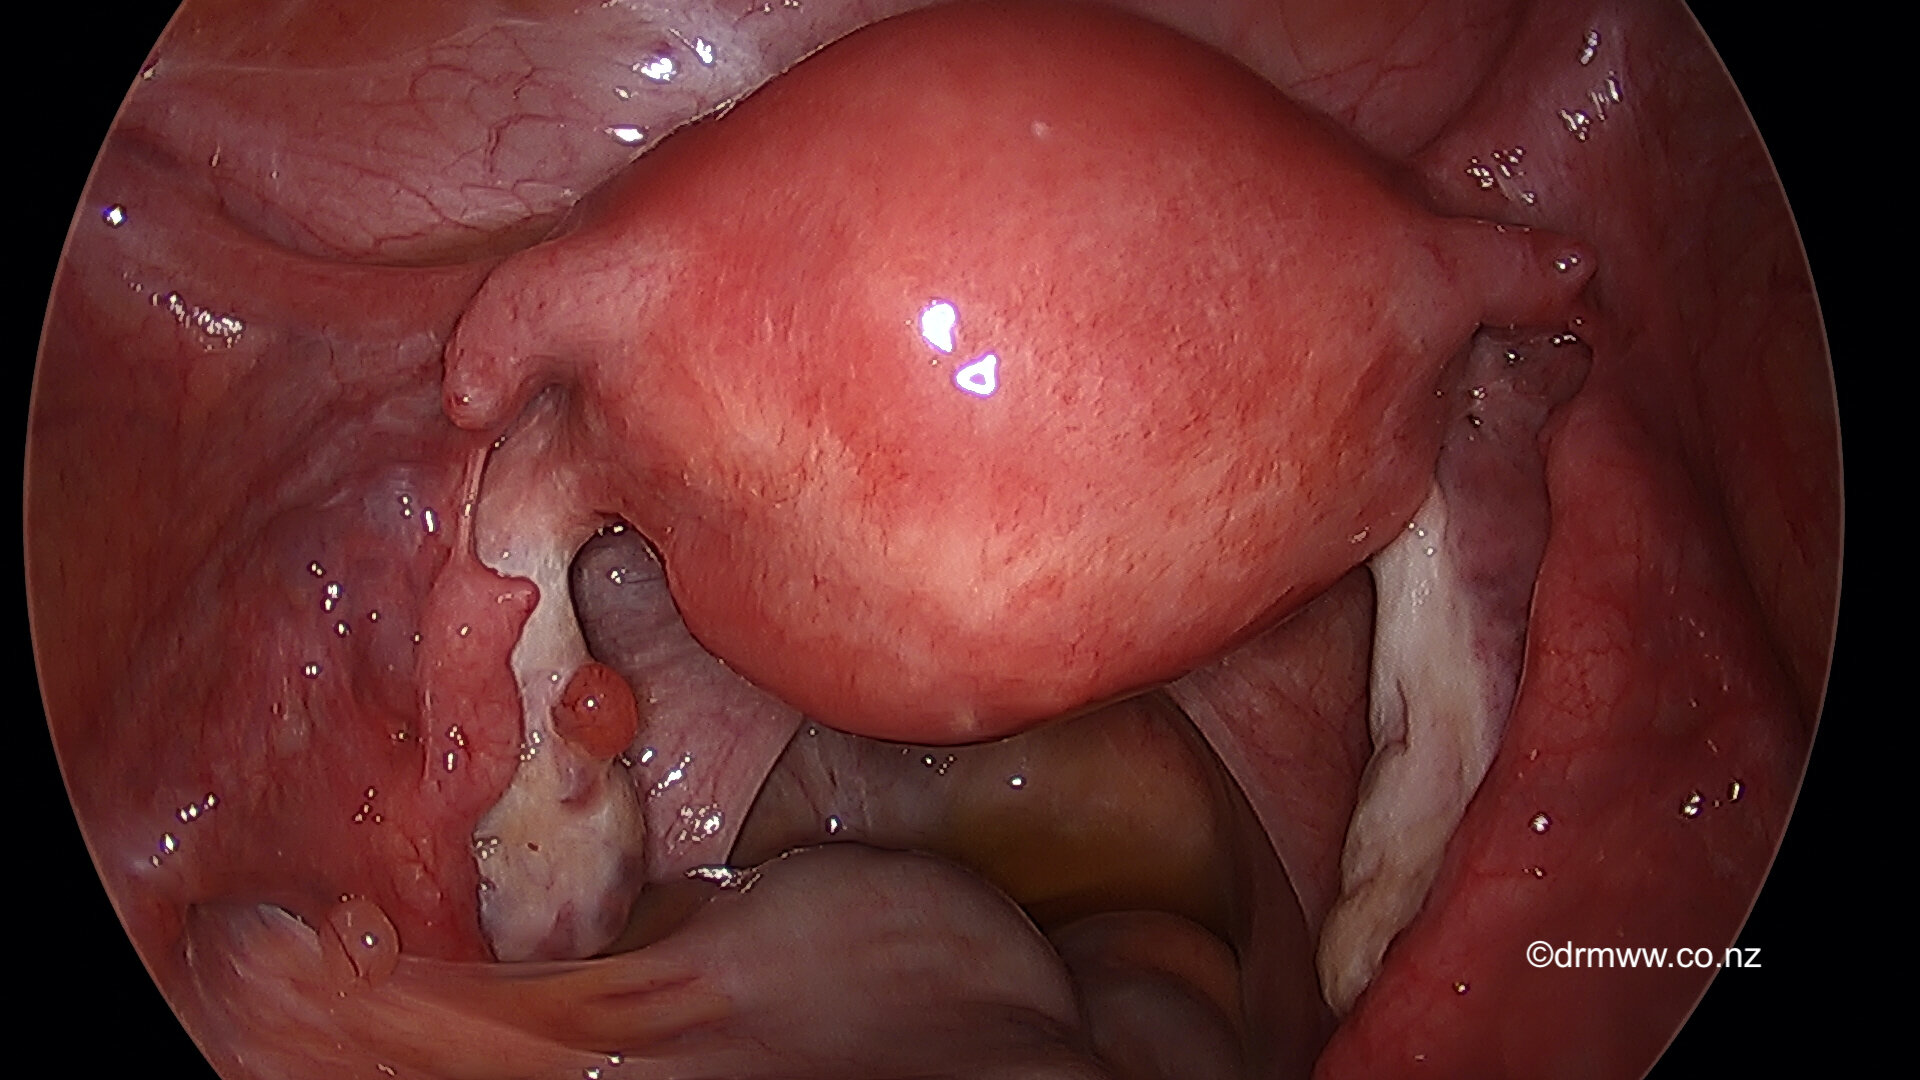

The Fallopian Tubes are rejoined after the laparoscopic repair